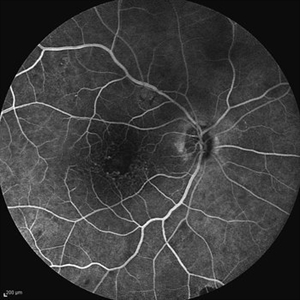

Behcet's Disease Behcet's DiseaseMar 13 2013 by Hamid Ahmadieh, MD Mid phase FA of the right eye of a 23-year-old man with retinal vasculitis and branch retinal vein occlusion (BRVO) due to Behcet's disease . Photographer: Solmaz Shahmohammad, Negah Eye Center, Tehran Imaging device: Heidelberg Spectralis Condition/keywords: branch retinal vein occlusion (BRVO), retinal vasculitis